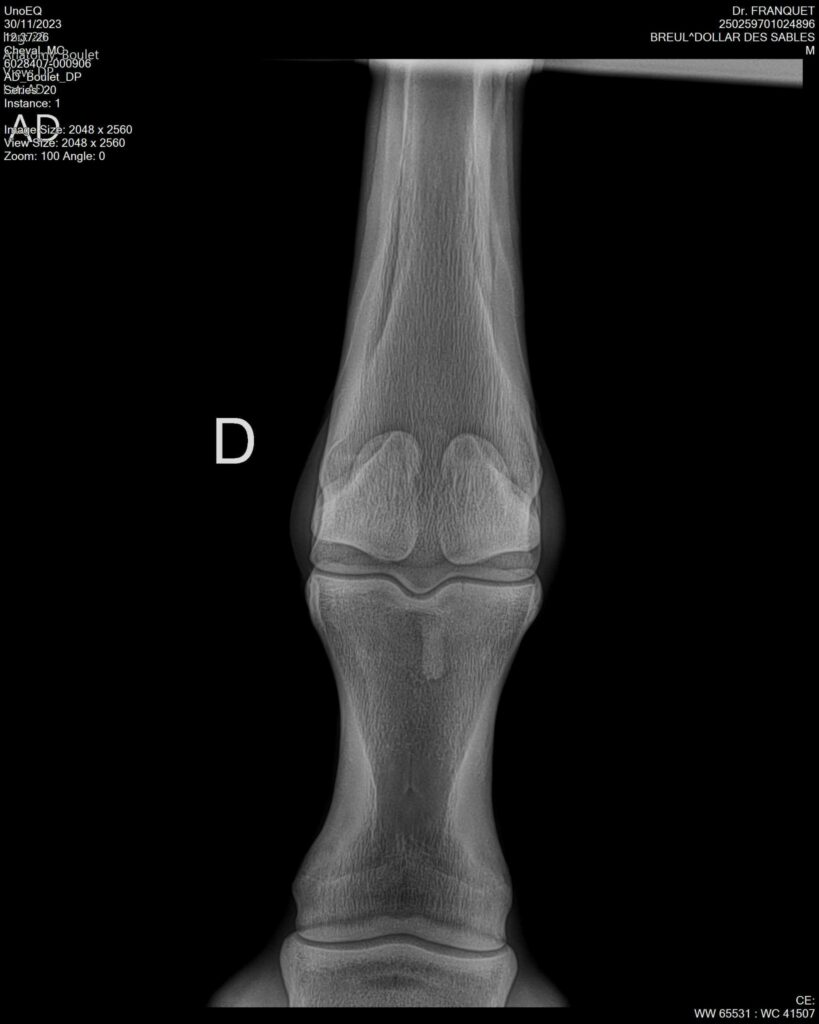

DOLLAR DES SABLES, Selle Français, hongre, 12 ans par DOLLAR DE MURIER x ABKE (ACORADO). Classé 135 avec professionnel à fait 125 avec amateur, récemment classé sur amateur 1GP 120. Très beau modèle ! Gentil cheval, respectueux avec des moyens et du sang. Transport OK, maréchalerie OK, santé RAS, Bilan clichés radios OK.

RADIOS